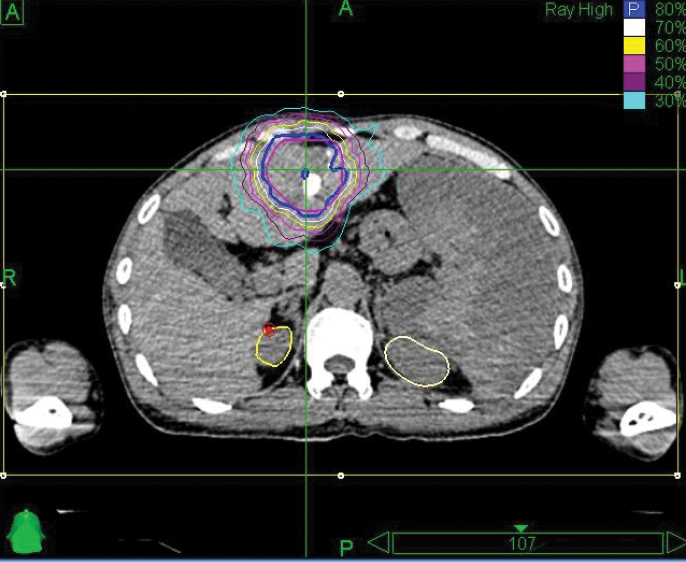

A 42-year-old male with chronic hepatitis B was initially diagnosed with primary liver cancer. He received radiofrequency ablation. Then an MRI revealed recurrence in front of the original lesion. The patient underwent interventional therapy in March 2012, but was hospitalized a month later when a CT showed a residual tumor and acute cholecystitis. Diagnosis was hepatocellular carcinoma, T2N0M0, Stage II. The patient was treated with the CyberKnife® System at 302 Hospital of PLA.

The initial follow-up took place four months after treatment, and CT showed no residual tumor. At the eight-month follow-up, MRI examination showed a region of necrosis in the location of the right lobe tumor. At 32 months post treatment an MRI showed no residual disease or any late toxicities.

“The CyberKnife System’s ability to track and adjust the beam with fiducials is key to giving high-dose SBRT to the liver.”

– Li Yu, M.D., Chairman, Radiation Oncology, 302 Hospital of PLA

Phase 1 treatment covered the right lower lobe and hilar nodes, divided into two targets. The prescription was 48 Gy, delivered in four 12 Gy fractions for each of the two targets. Bilirubin fluctuations were noted during the course of therapy, but gradually returned to normal after treatment. One month after radiotherapy, a CT scan showed tumor shrinkage. The left lobe had sufficiently enlarged in compensation, so the second stage of treatment was initiated.

Phase 2 treatment covered the right upper lobe, divided into two targets: The prescription was 39 Gy, delivered in three 13 Gy fractions for each of the two targets.